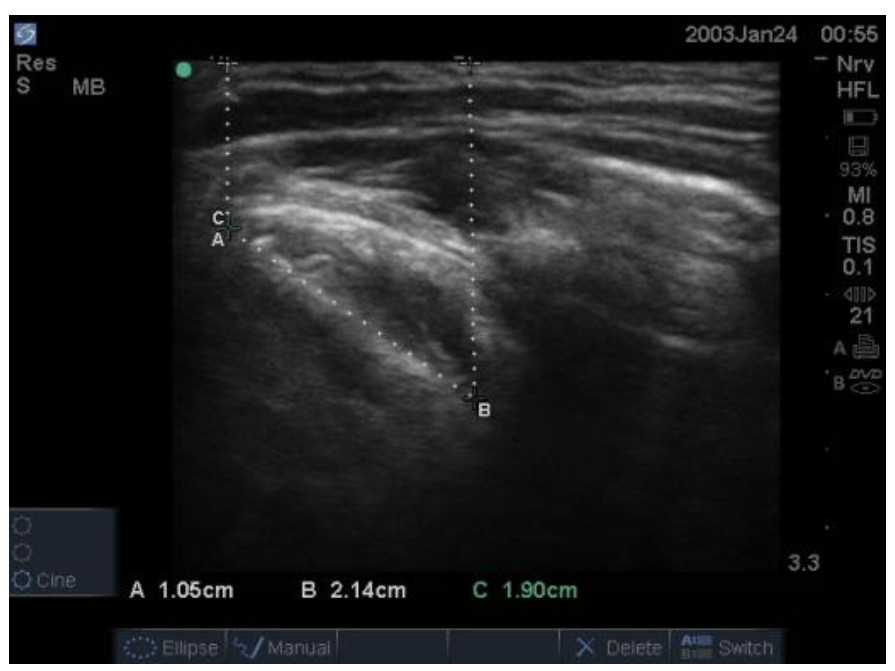

患者术后转入复苏室苏醒,清醒拔管后统一由具备10年以上临床麻醉经验及气道超声评估经验的麻醉医生(对分组情况完全盲态,且本研究所有测量及数据记录工作均由该医生独立完成)进行常规气道评估:张口度(mouth opening, MO)、甲颏间距(thyromental distance, TMD)、颈围(neck circumference, NC)、改良Mallampati分级(modified Mallampati classification, MMT)。之后由其继续进行超声气道指标的测量,患者取平卧、头后仰位,采用索诺声便携式彩超M-Turb(富士胶片索诺声股份有限公司、美国华盛顿州博塞尔市、美国)高频线阵探头测量会厌长度(length of the epiglottis, LE)、真声带长度(length of the true vocal cord, LV)、LE/LV、皮肤到真声带下缘的距离(distance from the skin to the inferior margin of the true vocal cord, DSIV)、皮肤到声带前联合的距离(distance from the skin to the anterior commissure of the vocal cords, DSAV)、DSAV/DSIV。具体测量方法如下:LE:线阵探头横置于患者下颌中线处平行下滑,在短轴平面找到低回声会厌结构。以中线为中轴逆时针旋转,可见会厌长轴平面结构,测量会厌的起点和终点之间的直线距离(图 1A)。LV:超声扫查侧方位甲状软骨侧板,将探头横置于一侧甲状软骨板上,测量真声带长度(图 2A)。DSIV:超声测量皮肤到真声带下缘的距离(图 2B)。DSAV:超声测量皮肤到声带前联合的距离(图 2C)。

| 注:A线为LE 图 1 LE的超声图像 Fig 1 Ultrasound image of LE |